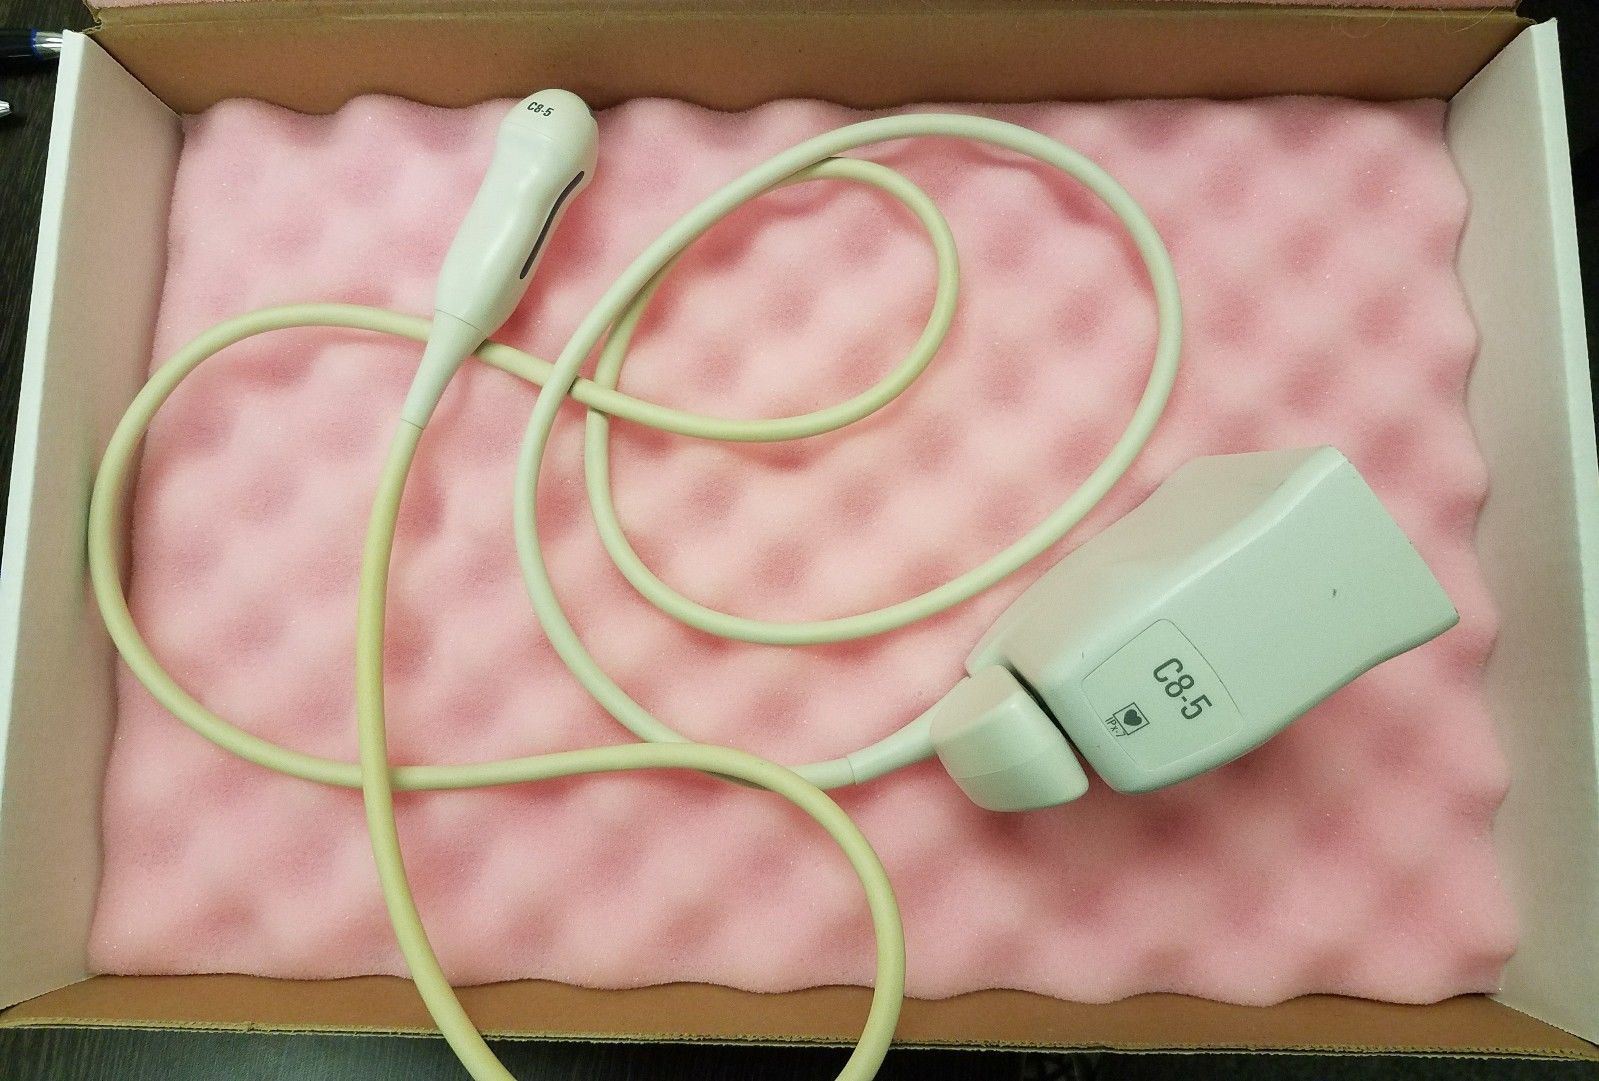

Philips Probes

Philips Probes

DIAGNOSTIC ULTRASOUND MACHINES FOR SALE